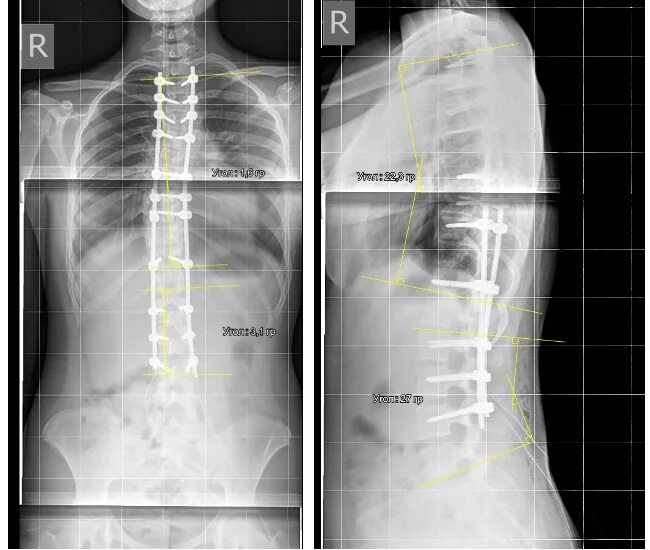

Сколиоз 2ст